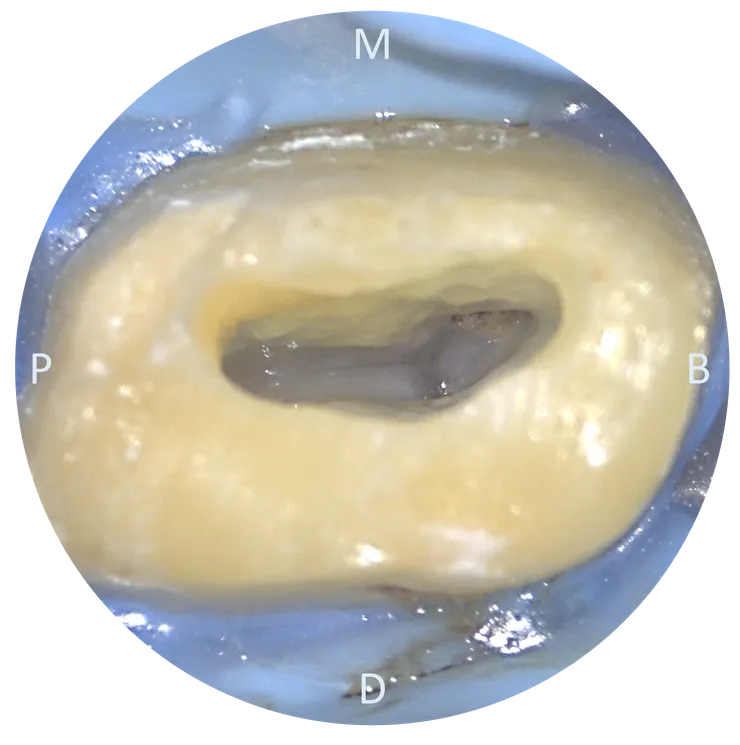

這是顆經過 prepare, fresh 的牙。

找到 chamber 後,先修形出理想的 outline form,讓 wall 在保留足夠厚度的同時,chamber 內也不要留下太多 undercut.

完成初步的 access cavity 後,可以看到 mesial wall 有非常突出的 dentin shelf 蓋住底下的 chamber floor.

車掉那片 dentin shelf 後,露出了 chamber floor.

此時隱約可以看到 P, DB, MB orifices.

繼續把 mesial wall 的 undercut 修掉, MB2 orifice 就顯露出來了。